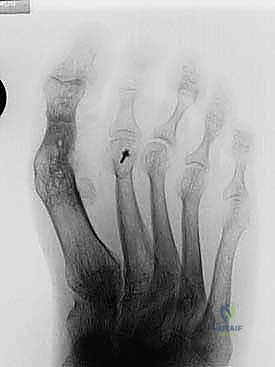

- التصوير بالأشعة السينية (X-rays): صور في وضعية الوقوف (تحمل الوزن) من زوايا متعددة لقياس زوايا التشوه بدقة وحساب مقدار الطول المفقود.

- الأشعة: يتم إجراء أول صورة أشعة سينية للمتابعة للتأكد من ثبات المسامير وبدء عملية الالتئام.